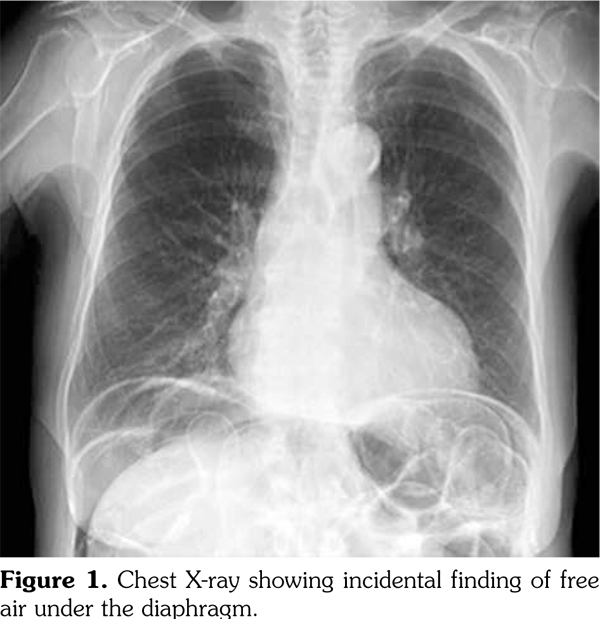

A 62-year-old female patient, diagnosed with mixed connective tissue disease (MCTD) five years priorly, presented with incidental findings of pneumoperitoneum on an outpatient chest X-ray (Figure 1). At initial diagnosis, she had inflammatory polyarthritis as evidenced by synovitis at the metacarpophalangeals and proximal interphalangeals bilaterally, Raynaud’s phenomenon, and swollen fingers (sausage appearance) with associated sclerodactyly. Serology showed positive anti-nuclear antibody (1:1200) and anti-ribonucleoprotein. All other autoantibodies were negative. She had initially been managed with oral steroids but was never on any immunosuppressant due to mild disease and patient preference. She had a history of vague abdominal discomfort, dysphagia and diarrhea since diagnosis, and did not report worsening of her baseline symptoms. On presentation to hospital, she was hemodynamically stable and her physical examination revealed a non-tender abdomen with no evidence of peritonitis. The patient had multiple comorbidities, which were severe chronic obstructive pulmonary disease, remote viral cardiomyopathy, small intestinal bacterial overgrowth (SIBO) and gastroesophageal reflux disease. She was not on corticosteroids, antibiotics or any immunosuppressant.

An abdominal computed tomography (CT) scan revealed large volume intra-abdominal free air, moderate intra-abdominal free fluid with no extravasated contrast, pneumatosis of the proximal jejunum with dilatation up to 5.8 cm, and a transition point (Figure 2). These findings raised concern for acute bowel ischemia, volvulus, and possible perforation.